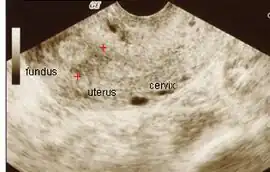

The history of a pregnancy event followed by a D&C leading to secondary amenorrhea or hypomenorrhea is typical. Hysteroscopy is the gold standard for diagnosis.[13] Imaging by sonohysterography or hysterosalpingography will reveal the extent of the scar formation. Ultrasound is not a reliable method of diagnosing Asherman's Syndrome. Hormone studies show normal levels consistent with reproductive function.

Ultrasound view. -

Hysteroscopic view.

-

Uterine cavity with uterine scarring -

Amniotic sheet on ultrasound